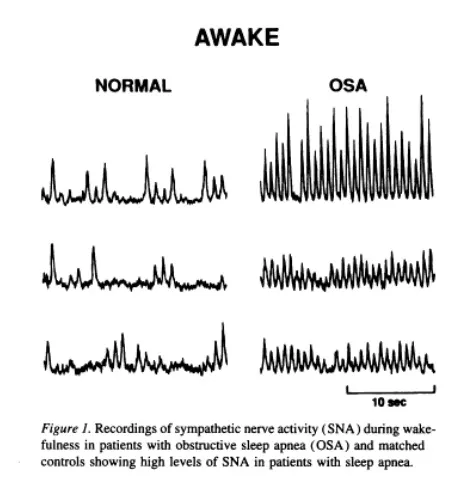

Die positive Nachricht: Therapeutische Maßnahmen zur Verringerung der SAS können diese Entwicklung aufhalten und umdrehen. Geduld und Befolgen der Therapie über längere Zeit sind jedoch absolute Voraussetzung dafür. (1)(4)(5)(6) Allerdings impliziert dies auch das Gegenteil: Bei SAS, die über Jahre andauert und nicht oder unzureichend behandelt wird, steigt die Wahrscheinlichkeit für Demenz und Alzheimer. (7)(8)(9) Wobei hier neben der mangelnden Regeneration und dem Sauerstoffmangel in der Nacht eine Überaktivität des Sympathikus als ursächlicher Faktor vermutet wird. (10)(11)(12)

(12) Somers VK, Dyken ME, Clary MP, Abboud FM. Sympathetic neural mechanisms in obstructive sleep apnea. J Clin Invest. 1995 Oct;96(4):1897-904. doi: 10.1172/JCI118235. PMID: 7560081; PMCID: PMC185826. – https://pubmed.ncbi.nlm.nih.gov/7560081/

Zu den häufigsten Begleiterscheinungen der Schlafapnoe gehört ein erhöhter Blutdruck. Nachts wird bei SAS-Patienten sehr oft ein deutlich erhöhter Blutdruck im Vergleich zu gesunden Personen gemessen. Dieser weist zudem deutliche Schwankungen auf, die mit dem Apnoe-Verlauf in Übereinstimmung gebracht werden können. Im Einzelfall konnten Forscher Spitzenwerte von 240/130 mmHg feststellen. (1) Besonders auffällig ist, dass der Bluthochdruck bei vielen Personen auch am Tag bestehen bleibt. Die Ursache scheint nicht nur der Atemstillstand und der Sauerstoffmangel zu sein, sondern auch eine in ähnlicher Weise erhöhte sympathische Aktivität.

(1) Somers VK, Dyken ME, Clary MP, Abboud FM. Sympathetic neural mechanisms in obstructive sleep apnea. J Clin Invest. 1995 Oct;96(4):1897-904. doi: 10.1172/JCI118235. PMID: 7560081; PMCID: PMC185826. – https://www.ncbi.nlm.nih.gov/pmc/articles/PMC185826/?page=2

Nachgewiesen ist bei SAS-Patienten eine erhöhte Sympathikusaktivität in der Nacht und auch noch im Wachzustand gegenüber gesunden bzw. übergewichtigen Personen ohne SAS. Markant sind die extremen Spitzenwerte, die während Apnoe-Phasen beobachtet werden können (bis zu +200%). (1) Interessanterweise konnten keine Korrelationen zwischen der erhöhten Sympathikusaktivität und Body-Mass-Index, AHI und Blutdruck gezeigt werden. Damit ist die erhöhte Sympathikusaktivität möglicherweise ein Symptom des Stresses, welches die Atemstillstände dem Körper vermitteln.

Quellen

(1) Somers VK, Dyken ME, Clary MP, Abboud FM. Sympathetic neural mechanisms in obstructive sleep apnea. J Clin Invest. 1995 Oct;96(4):1897-904. doi: 10.1172/JCI118235. PMID: 7560081; PMCID: PMC185826. – https://www.ncbi.nlm.nih.gov/pmc/articles/PMC185826/?page=2